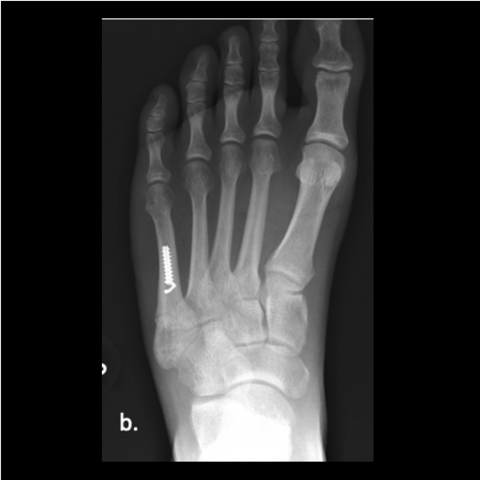

Figure 2a

Figure 2a. A 30-year-old male soldier was injured playing basketball, as shown in this film taken upon injury. We fixated his fracture with a solid screw system. He returned to full duty in 4 months and was pain-free in days after his surgery.